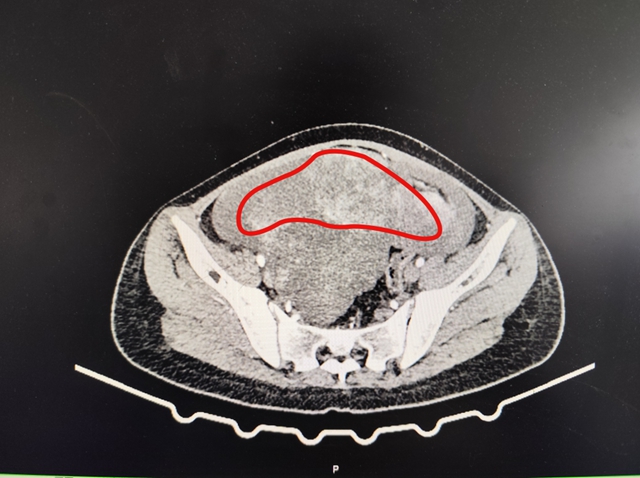

为了让小敏得到及时诊治,家人带着她到西南医科大学附属中医医院就诊。门诊完善肿瘤标志物检查后,结果提示CA125高达175.00IU/ml(远超正常范围);妇科彩超进一步显示,盆腔内有巨大实性肿物,且存在盆腔积液。进一步检查发现,肿瘤最大直径接近20CM,且并非单一肿物,整个腹腔内都布满了肿瘤。结合腹部增强CT检查,考虑恶性肿瘤性病变的可能性较大。

圈出部分为肿瘤区域